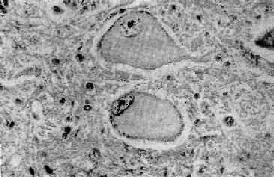

中央Nissl小体溶解

图16-1 中央Nissl小体溶解

神经细胞肿胀,胞核偏位,Nissl小体仅见于细胞周边部

1.中央性Nissl小体溶解(central chromatolysis)这是一种可逆性变化,病因一旦去除,就可恢复正常,如病变继续发展,则可导致细胞的萎缩和死亡。常见的病因有病毒感染(如脊髓灰质炎病毒)、维生素B属缺乏、坏血病和神经元与轴突断离。病变表现为神经细胞肿胀,丧失典型的多极形状而变为圆形,胞核偏位,胞浆中央的Nissl小体崩溃成为细尘状颗粒,进而完全溶解消失,或仅在细胞周边部有少量残余。胞浆着色浅而呈苍白均质状(图16-1)。